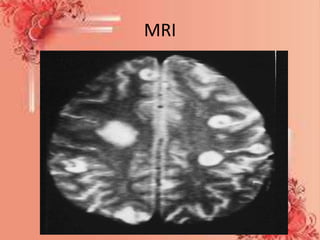

• MRI (magnetic resonance imaging) scan - an MRI

machine uses a magnetic field and radio waves to

create detailed images of the inside of the body.

Unlike CT scanning or general x-ray studies, no

ionizing radiation is involved with an MRI. It is a

painless procedure

MRI

Diagnostic test • Bloodtest - to determine whether there is an infection. If results show elevated levels of white- blood cells, there most probably is an infection. • Chest X-ray - to determine whether the patient has a lung infection. Imaging scans: • MRI (magnetic resonance imaging) scan - an MRI machine uses a magnetic field and radio waves to create detailed images of the inside of the body. Unlike CT scanning or general x-ray studies, no ionizing radiation is involved with an MRI. It is a painless procedure